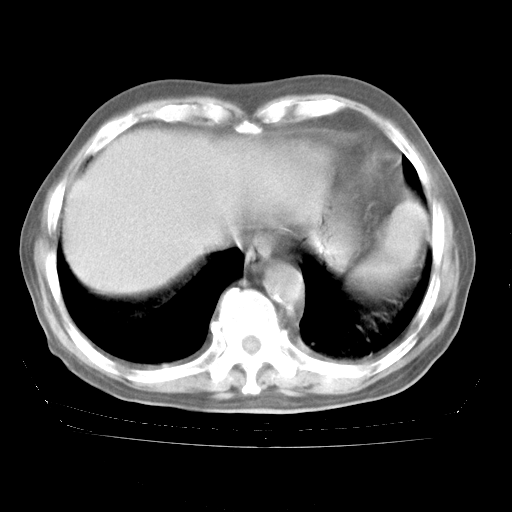

4月28日肺部CT